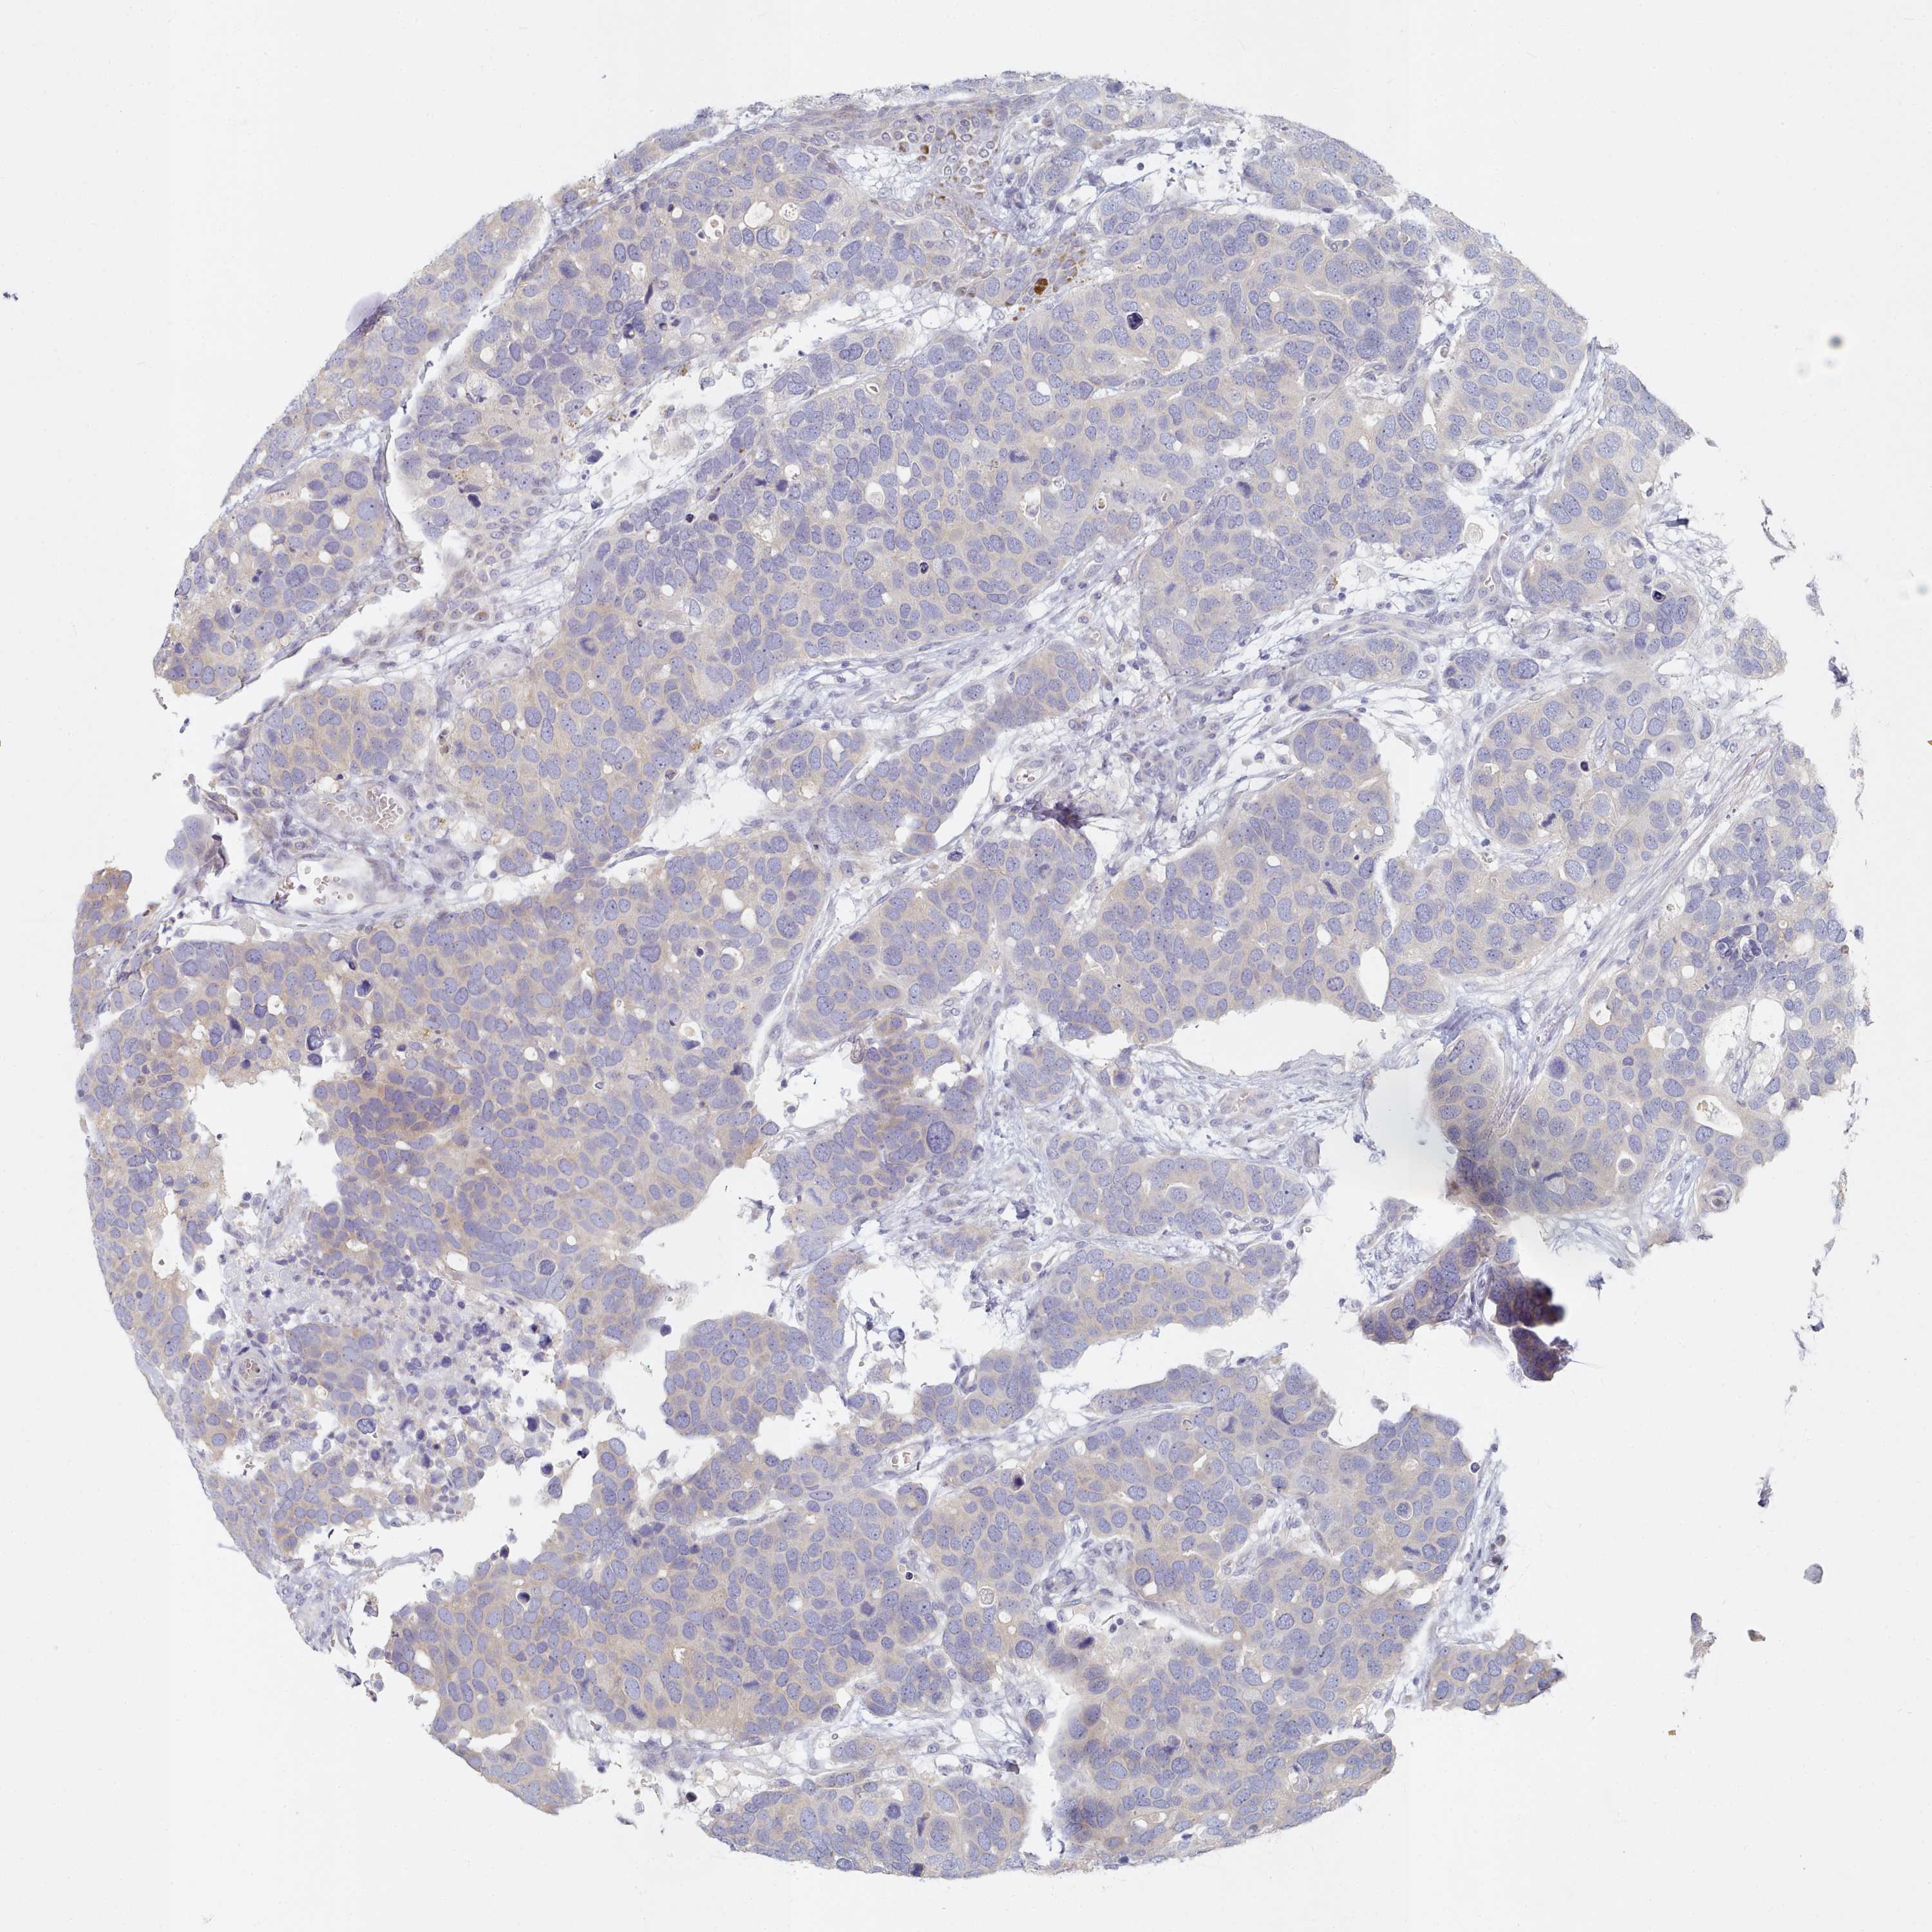

CANCER BREAST CANCER Show tissue menu

BRCA TCGA BRCA VALIDATION PROTEIN EXPRESSION

TYW1B is not prognostic in Breast Invasive Carcinoma (TCGA)